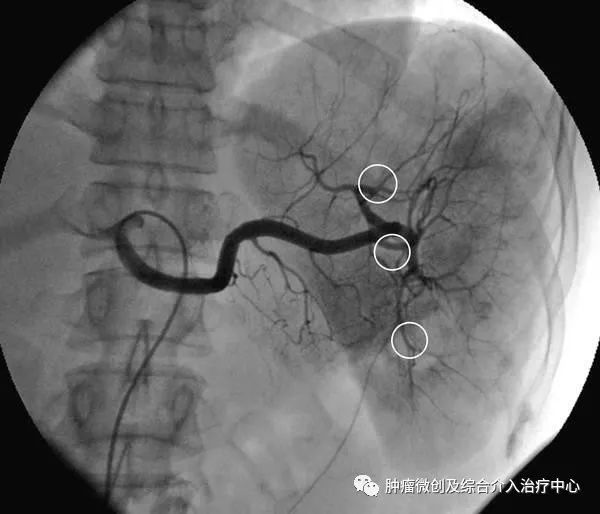

2.借助导丝将导管超选至脾动脉造影,以每秒5~8ml,总量15~30ml注入造影剂,观察脾脏的大小及脾内病变情况,脾破裂可见造影剂外渗、血管离断等影像改变。

3.根据脾脏病变及不同的栓塞方法选择栓塞材料。部分脾动脉栓塞多采用明胶海绵颗粒,约2mm3,浸入含青霉素和庆大霉霉素的生理盐水中;也有主张用明胶海绵短条,约2mm×8mm大小,插入2ml注射器乳头中注入,一般为6~8条。栓塞时导管尽量超选至深处,最好越过胰背动脉,以防误栓造成医源性胰腺炎。术中通常根据脾动脉的血流来判断脾脏栓塞程度,笔者的经验是脾动脉血流稍减慢栓塞范围为30%~40%,明显减慢为50%~60%,若短暂停流后呈蠕动前进为70%~80%。全脾栓塞时多采用明胶海绵粉末或无水乙醇,导管超选应更为准确、深入,必要时可通过3F微导管或球囊导管注入无水乙醇等液态栓塞剂,以免反流。脾动脉主干栓塞时多选用不锈钢螺圈,栓子直径应略大于脾动脉管径,导管置于脾动脉近端,但仍应越过胰背动脉开口。

4.再次脾动脉造影,明确脾栓塞程度。若感不足,可补加栓塞,直至满意为止。退出导管,穿刺处压迫止血后加压包扎,平卧24h。